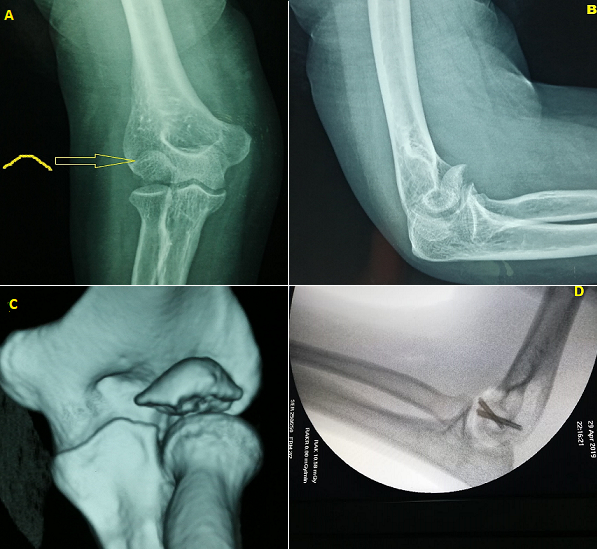

A 42-year-old man presented to the emergency department for pain at his right elbow following a fall from a bicycle onto the outstretched hand. A radiograph of the elbow was performed then an oral analgesic was prescribed with splint elbow to body. At home, the pain has decreased in intensity but it increased when he mobilized his elbow. 3 days later, he consulted our department of orthopedics for the persistence of elbow pain. Upon admission, physical examination revealed mild swelling and tenderness over the lateral aspect of the distal part of his humerus. Mobilization of the elbow was painful. The neurovascular exam was normal. X-rays of the elbow showed a displaced capitellar fracture (A, B). 3D computed tomography confirmed the type I Hahn fracture with no other lesion (C) prompting the patient to undergo surgery. A lateral approach was performed. The intra-operative aspect showed a separated capitellum from the humeral shaft then an internal fixation of the fracture using two Herbert screws was performed (D). The patient was reviewed one week later; the physical examination found no infection and neurovascular examination was normal, the x-ray control was good and rehabilitation of the elbow allowed. At three months of follow up, our patient presented a good outcome with no pain and he had regained full activities.